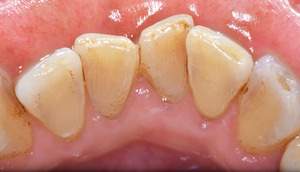

歯石除去

治療前

治療後

| 年齢 | 40歳・男性 |

|---|---|

| 主訴 | 歯石をとりたい |

| 治療内容 | 歯石除去 |

| 治療期間 | 30分 |

| 費用 | 約2,000円 |

| リスク・副作用 | ・歯ぐきの炎症が強いと歯石を取る際に出血することがあります。 ・処置後に歯がしみることがあります。 ・歯と歯の間に隙間ができるので、息が漏れ発音しにくいと感じることがあります。 ・歯ぐきの炎症が軽減すると歯ぐきが引き締まり、歯が長く見えることがあります。 |